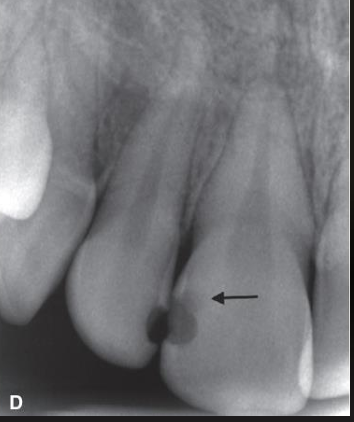

what are the arrows pointing to?

incipient interproximal caries